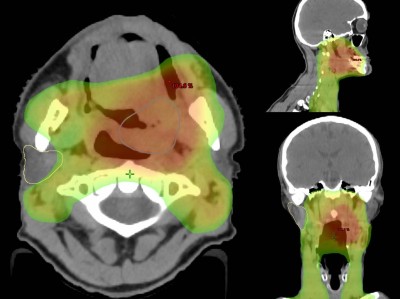

Neues in der Radiochemotherapie von Kopf-Hals-Tumoren

Erste Studien deuten darauf hin, dass eine Deeskalation der Radiochemotherapie bei nichtmetastasierten Kopf-Hals-Tumoren möglich ist – insbesondere bei HPV-positiven Karzinomen. Hypoxiesensitive Bildgebung könnte die Patientenselektion unterstützen. Gleichzeitig zeichnet sich die perioperative Checkpointinhibition als potenzieller neuer Standard bei resektablen HNSCC ab.

Eine ältere Frau schaut in die Ferne/© RgStudio / Getty Images / iStock (Symbolbild mit Fotomodell), Bestrahlungsplans einer Wirbelsäulenmetastase eines oligometastasierten Prostatakarzinoms/© Springer Medizin Verlag GmbH, Immuncheckpointinhibitoren binden an Krebszelloberflächenproteine /© Juan Gärtner / stock.adobe.com, Arzt misst Blutzucker per Glucometer/© geargodz / Stock.adobe.com (Symbolbild mit Fotomodell), Ein Anatomie-Modell des Kopfes in der HNO-Praxis/© peakSTOCK / Gettty Imgaes / iStock (Symbolbild mit Fotomodellen), Larynxkarzinom/© Springer Medizin, Tropf in Krankenhaus/© Amornrat Phuchom / Getty Images / iStock, Infusionstropf im Krankenhaus /© Trsakaoe / stock.adobe.com, Zytologischer Abstrich bei gynäkologischer Untersuchung/© Iryna / stock.adobe.com (Symbolbild mit Fotomodell), Pembrolizumab-Modell (Illustration)/© Kateryna_Kon / stock.adobe.com, Plattenepithelkarzinom des Oropharynx/© Springer Medizin Verlag GmbH, Tumor im linken Kleinhirnbrückenwinkel und inneren Gehörgang (linkes Bild) und Tumor am Foramen jugulare (rechtes Bild)/© Springer Medizin, Frau erhält Infusion/© Eakkachai / Stock.adobe.com (Symbolbild mit Fotomodell), Raumforderung im Ohr/© Franzen A M und Coordes A / all rights reserved Springer Medizin Verlag GmbH, Blumenkohlartiger Knoten am Hinterkopf/© Winkler D. et al. doi.org/10.1007/s00105-024-05437-1 unter CC-BY 4.0, 18-FDG-PET-Fusions-CT vom Kopf/© Sheila Büchel u. Markus Jungehülsing doi.org/10.1007/s00106-024-01459-2 unter CC-BY 4.0, VMAT-Bestrahlungsplan einer definitiven Radiochemotherapie eines linksseitigen, lokal fortgeschrittenen Tonsillenkarzinoms/© Schnellhardt, S et al. / all rights reserved Springer Medizin Verlag GmbH, Search Icon, Einem Mann wird Blut abgenommen/© auremar / stock.adobe.com (Symbolbild mit Fotomodellen), Frau wird Blut abgenommen/© andresr / Getty Images / iStock (Symbolbild mit Fotomodellen), Eine Frau erhält eine Chemotherapie/© peopleimages.com / stock.adobe.com (Symbolbild mit Fotomodell)